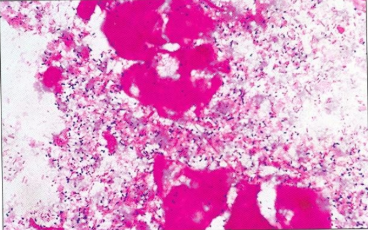

E. rhusiopathiae in a Gram-stained smear from a

culture. There are small Gram-positive rods but also

some short filaments indicating that the colonies are

changing to the rough form.